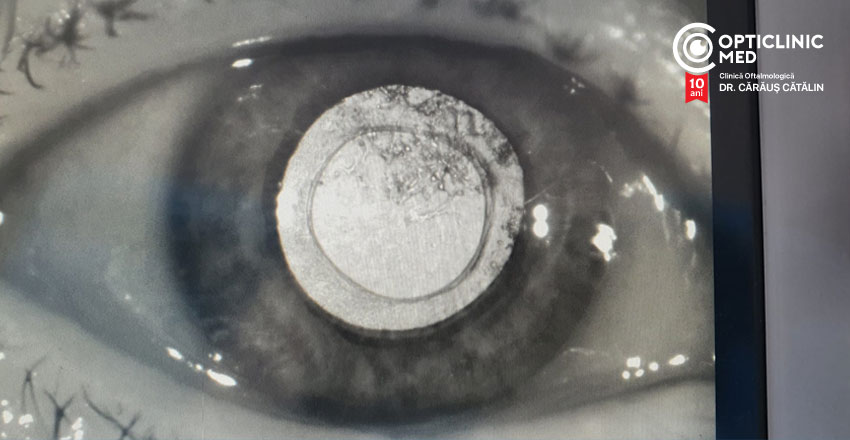

LASER-ul YAG realizează o breșă centrală în sacul cristalinian, în partea posterioară opacifiată, permițând astfel luminii să ajungă la nivelul retinei.